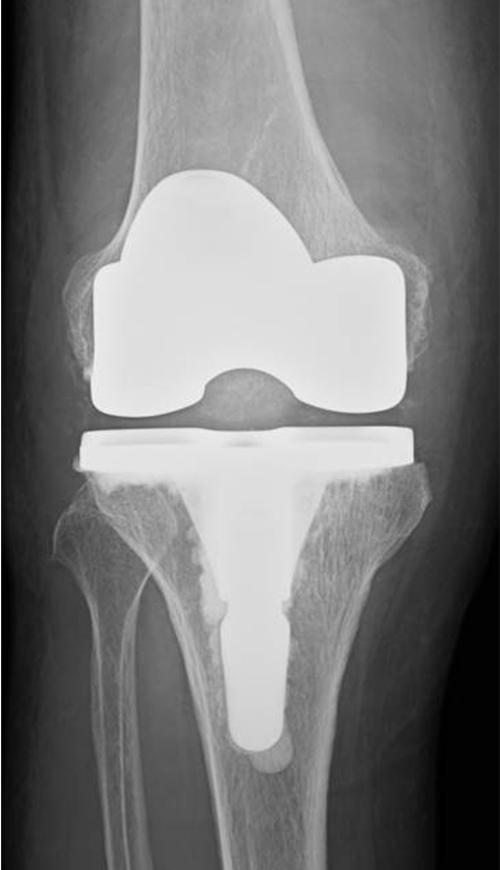

傷んだ関節表面を人工関節の形に合わせて削り、金属、セラミック、ポリエチレンでできた人工関節を骨の上に固定します。この手術を受けることで、関節の動きが滑らかになり、O脚やX脚といった変形が改善し、まっすぐな脚にすることが出来ます。人工関節の耐久性は10年間弛みなく日常生活が送れる可能性が95%以上といわれ、長期的にも安定した方法です。さらに最新の人工関節では性能が格段に良くなっており、20〜30年以上の機能することも十分期待できるようになってきました。

当院にて右人工膝関節全置換術(TKA)を施行。術前、歩行も困難でしたが、術後は杖歩行も安定し、良好な可動域も獲得。入院中に反対側の人工膝関節単顆置換術(UKA)も行い、十分なリハビリ後に退院となりました。

当院にて人工ひざ関節全置換術(TKA)を施行。入院中に両側の手術を行い、術中に神経ブロックを併用しています。

〈手術後のレントゲン〉

右TKA後

左TKA後

当院にて人工ひざ関節全置換術(TKA)を施行。両側の手術を同時に行いました。両側同時手術の場合でも入院期間は片側手術の場合と大きく変わらず(プラス1週間程度)、麻酔も1回で済むために身体的、経済的な負担の軽減を期待できます。また両ひざが同程度に悪いケースも少なくなく、同時に行うことで左右のバランスが良くなるためにリハビリをスムーズに進めることが可能となります。